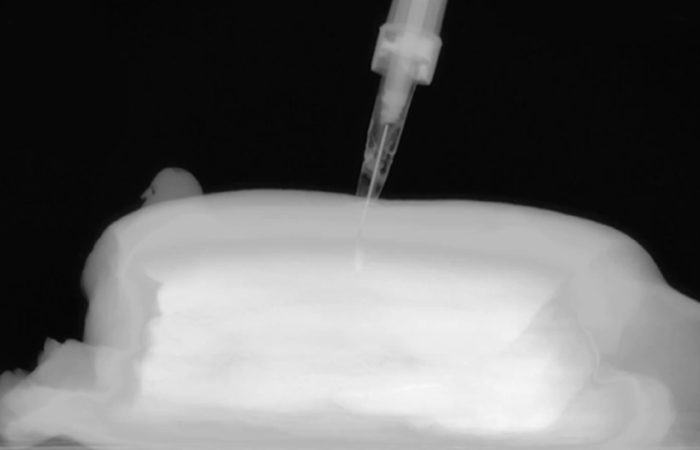

In recent years, a novel, implant-based methodology has been in development for releasing anti-VEGF medication at a slow, steady rate over a long period of time (Figures 1 & 2). This technology is being developed both to extend the time between patient visits and to facilitate steady state medication release, which may help physicians control disease progression in a more even, predictable way.

Figure 2: Injector used to insert the ophthalmic implants.